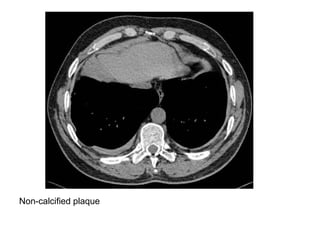

Calcified plaque

Non-calcified plaque